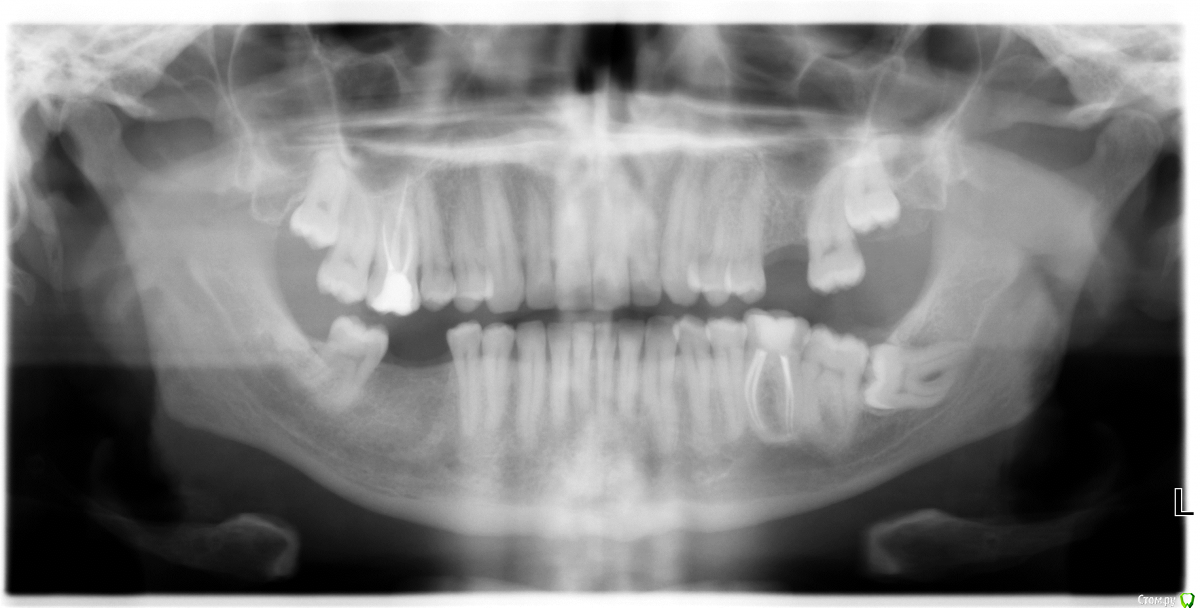

Ganj Опубликовано 21 июля, 2020 Поделиться Опубликовано 21 июля, 2020 (изменено) Уважаемые врачи, добрый день!Я переезжаю в другую страну, стоматология там очень дорогая, поэтому решил по максимуму сделать работы по зубам в России (МСК). Ходил на консультацию по поводу имплантации нижней шестерки и заодно обсудил с хирургом свою злосчастную ретинированую восьмерку снизу.Она полностью под десной и как мне казалось, держит под десной еще соседнюю семерку. Хирург сказал, что ничего восьмерка не держит, все норм (хотя семерка почти тоже под десной), если не беспокоит, то восьерку лучше вообще не удалять, так как есть риски: зуб лежит на нерве и риск повредить нерв высок; придется спиливать значительную часть кости при удалении зуба и есть риск перелома челюсти; зуб большой и занимает много места и является солидной частью челюсти, после удаления когда буду что-то жевать, то возможен перелом. В общем ввязываться в авантюру без необходимости крайне не советовал, так как есть много "но", а результат достаточно сомнительный. Также сказал, что если буду все-таки удалять, то обязательно КТ (для имплантации КТ не попросил). Собственно вопрос, как быть? Я понимаю, что это бомба замедленного действия и рано или поздно я получу там очаг, но решиться по сути на перелом челюсти мне тяжело. Также я понимаю, что сколько людей столько и мнений, но я готов выслушать любой совет, так как у самого компетенций нет. Изменено 21 июля, 2020 пользователем Ganj Ссылка на комментарий

red_butler Опубликовано 22 июля, 2020 Поделиться Опубликовано 22 июля, 2020 По панорамному снимку можно судить только о высоте, с этим нет проблем. Предположу что визуально и с шириной проблем нет, в этом случае Кт и шаблон не обязательны. Для более точного ответа выкладывайте фото Ссылка на комментарий